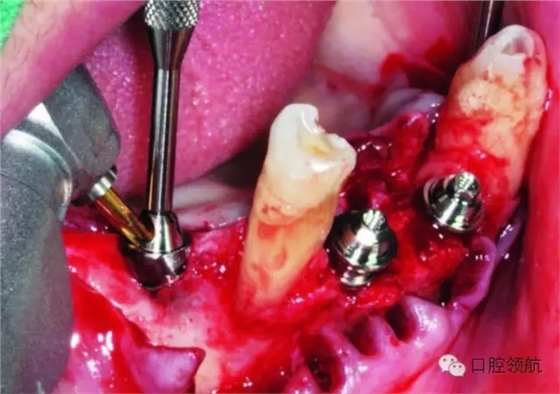

角度復(fù)合基臺(tái)除了與種植體固定的螺絲外,還有一個(gè)與修復(fù)體就位方向一致的金屬手柄。先用金屬手柄試戴角度復(fù)合基臺(tái)的方向,確定后用螺絲刀旋緊植體固定螺絲,然后反轉(zhuǎn)拆卸金屬手柄(圖4-26,圖4-27)。

圖4-26 確認(rèn)與對(duì)頜牙的關(guān)系

圖4-27 旋緊30°角度復(fù)合基臺(tái)